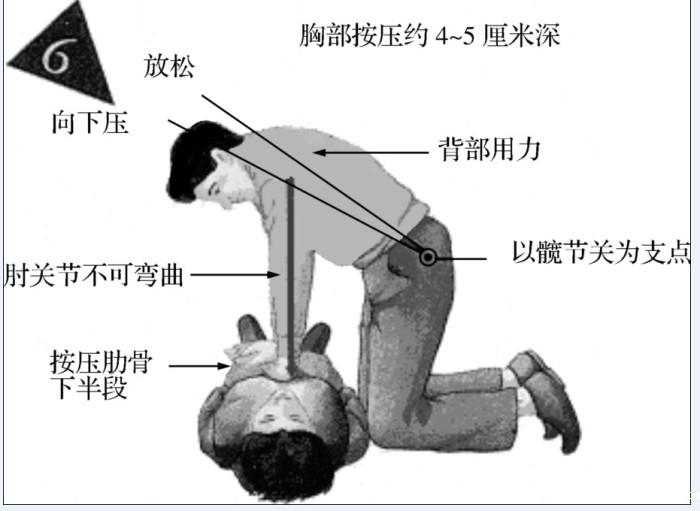

施救者面向病人跪着,两腿打开,与肩同宽,肩膀在伤患胸骨的正上方,双臂伸直,用体重的力量,直接下压,压力推至胸骨上。

每次下压时,应将胸骨压下4~5厘米,放松时,手不施压力,但不可移动手的位置。